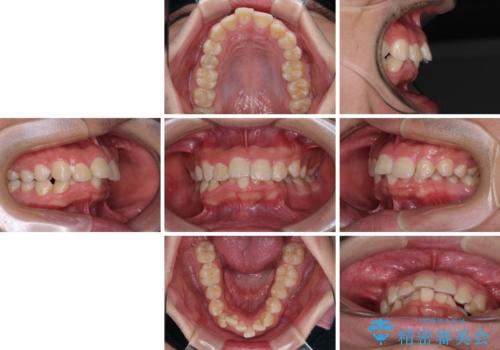

- デコボコと奥歯の咬み合わせのズレを気にして来院された患者様です。

骨格的に、下顎が右側にずれており、左側の咬み合わせに鋏状咬合などのアンバランスが生じている状態でした。

また、上顎前歯に欠損が1本あり、上下ともに前歯部に叢生が認められ、下顎前歯の大半が隠れてしまうほどの過蓋咬合も認められました。

咬合平面を平坦にしながら前歯の咬み合わせを挙上し、デコボコと鋏状咬合も改善していくこととしました。

骨格的な左右差が大きかったため、上下の正中のズレや、左右奥歯の咬み合わせなどは妥協的な仕上がりとなりました。

骨格的なズレに対応するにはワイヤー矯正が至適であり、マウスピース矯正は選択しないようにお話をしました。